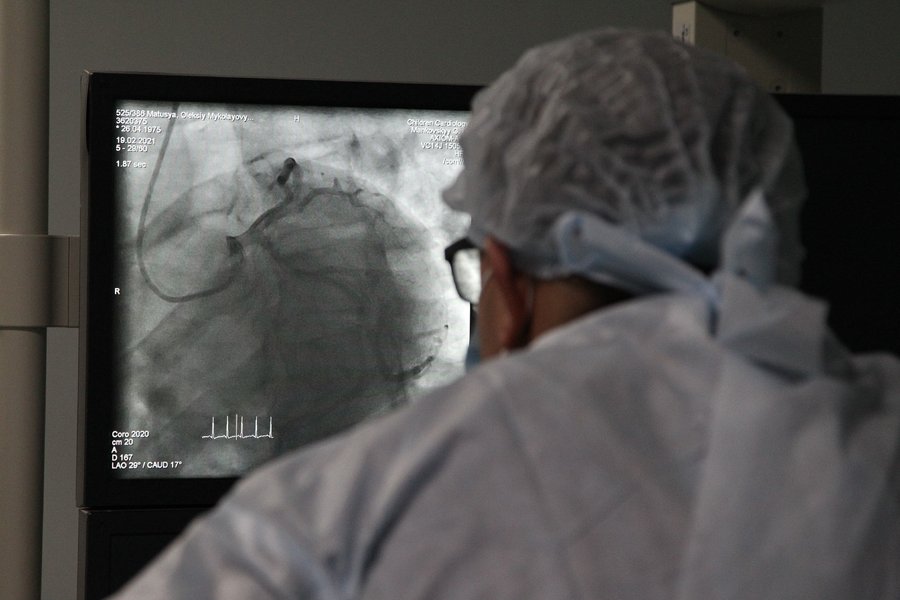

Операционная похожа на те, что показывают в западных сериалах о медицине. Возле высокой кровати — несколько мониторов на подвижном кронштейне, у изголовья — похожий на огромные наушники рентгеновский аппарат, который просвечивает грудную клетку, картинку выводят на мониторы. Время от времени аппарат вращают, чтобы осмотреть сердце с разных сторон.

К операционной примыкает пультовая, из нее сквозь большое окно можно видеть все, что происходит во время операции. В пультовой также есть несколько мониторов, с их помощью наблюдают за состоянием пациента и манипуляциями докторов. Попутно ведется видеозапись. Потом один диск остается в истории болезни, а второй дарят пациенту на память.

Прогрессивная рутина. Малоинвазивную диагностику и операции в Центре делают каждый день, эти вмешательства длятся в среднем полчаса

В течение дня Георгий Маньковский постоянно курсирует между стационарами и вторым этажом, где расположены операционные и реанимации — детская и взрослая. Его специализация — интервенционная кардиология, в особенности малоинвазивные операции. Поэтому он и сам их проводит, и как самый опытный специалист наблюдает за коллегами, дает им советы или приходит на помощь в трудные моменты. Маньковский говорит, что всегда полезно "сменить руку", если, к примеру, у врача есть сложности с продвижением катетера или заходом в особенно узкий сосуд. В его отделении коронарография, то есть проверка сосудов сердца, как и установка стентов, — рутинные процедуры, которых может быть до десятка в день.